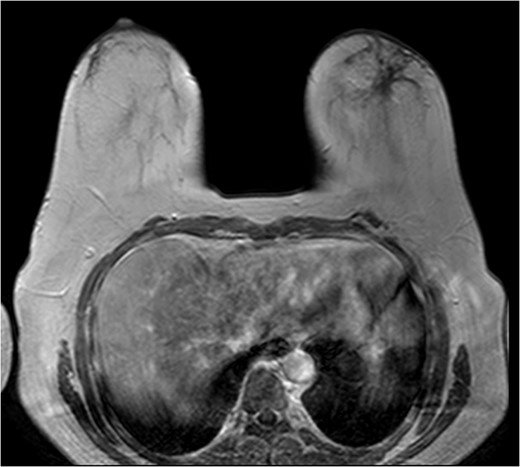

The patient was then sent for MRI of the breast to detail the extent of the remaining mass. This revealed an ill-defined mixed linear and fine nodular enhancing tumor 6.5 × 4.6 × 4.8 cm in size with BI-RADS 5 (Figs 4–7).

The role of MRI in identifying the extent of breast carcinoma is widely reviewed. EPC has been noted to have multifocal hyperintensities at T1 weighted imaging. Contrast MRI will reveal enhancement of the cystic wall, septa and mural nodules [4].